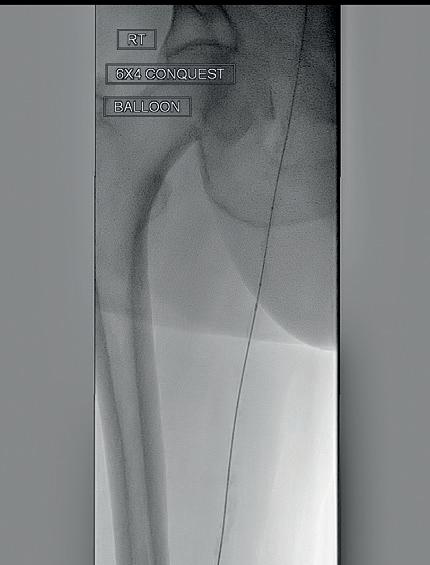

PERIPHERAL IVL

Shockwave Peripheral IVL: Reliably safe. Predictably effective. Backed by real-world and level one evidence, Shockwave IVL modifies both superficial and deep calcium. Designed for the iliacs, fem-pop and below-the-knee arteries, these purpose-built devices come in sizes that allow you to treat calcium at any level. So you can count on affecting outcomes for the better.

Peripheral Important Safety Information

In the United States: Rx only.

Indications for Use—The Shockwave Medical Intravascular Lithotripsy (IVL) System is intended for lithotripsy-enhanced balloon dilatation of lesions, including calcified lesions, in the peripheral vasculature, including the iliac, femoral, ilio-femoral, popliteal, infra-popliteal, and renal arteries. Not for use in the coronary or cerebral vasculature.

Contraindications—Do not use if unable to pass 0.014” (M5, M5+, S4) or 0.018” (L6) guidewire across the lesion-Not intended for treatment of in-stent restenosis or in coronary, carotid, or cerebrovascular arteries.

Warnings—Only to be used by physicians who are familiar with interventional vascular procedures—Physicians must be trained prior to use of the device— Use the generator in accordance with recommended settings as stated in the Operator’s Manual.

Precautions—use only the recommended balloon inflation medium—Appropriate anticoagulant therapy should be administered by the physician—Decision regarding use of distal protection should be made based on physician assessment of treatment lesion morphology.

Adverse effects–Possible adverse effects consistent with standard angioplasty include–Access site complications –Allergy to contrast or blood thinner–Arterial bypass surgery—Bleeding complications—Death—Fracture of guidewire or device—Hypertension/Hypotension—Infection/sepsis—Placement of a stent—renal failure—Shock/pulmonary edema—target vessel stenosis or occlusion—Vascular complications. Risks unique to the device and its use—Allergy to catheter material(s)— Device malfunction or failure—Excess heat at target site. Prior to use, please reference the Instructions for Use for more

contraindications,